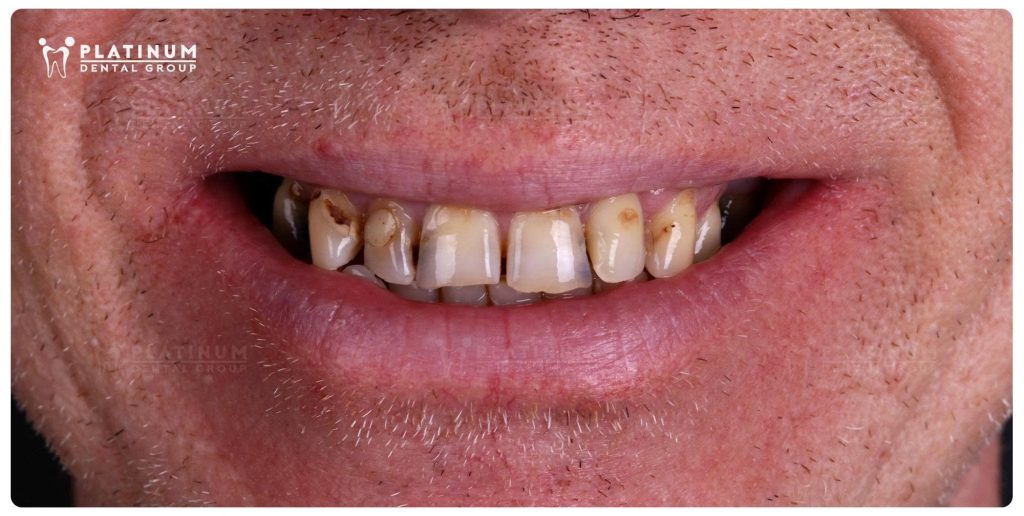

“Wow… this is incredible. Looking at my smile before and after treatment, I honestly feel emotional. I look so different.”

At 55 years old and visiting from the UK, Mr. Jeffrey came to us with a simple wish one that had been put off for years: to smile confidently again.

For a long time, he had been living with missing back teeth, while several of his remaining teeth were badly decayed and fractured. Over time, this affected far more than just the appearance of his smile. His chewing function had become seriously compromised, meals were no longer enjoyable, and his confidence had gradually faded.